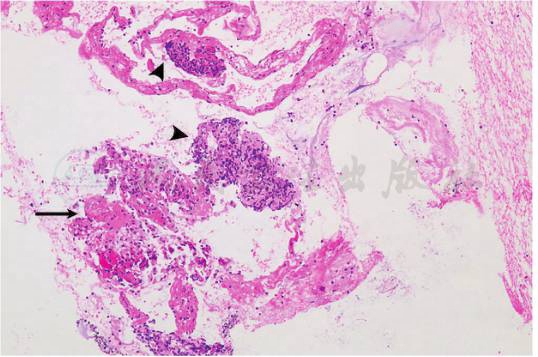

病理结果(图5):穿刺组织可见慢性肉芽肿性炎症,纤维素性渗出及坏死。未见明显核异型上皮成分。 免疫组化结果:CK(+),VIM(-),CgA(-),Syn(-),TTF-1(-),WT-1(-),LCA(-),P63(-),Napsin A(-),P40(-)。 特殊染色结果:抗酸(-),PAS(-),银染(-)。

图5 活检组织内可见(HE,×100):慢性肉芽肿性炎症(箭头),纤维素性渗出及坏死(黑箭)

引自:主编:.呼吸与危重症医学疑难与危重病例精选.第1版.ISBN:978-7-117-30147-3